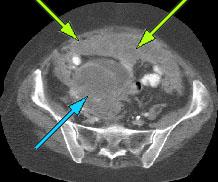

HELICAL CT FINDINGS: The CT was performed on AIC’s multi-slice helical CT (MSCT) scanner. Images with 5 mm collimation were obtained before, immediately following and 5-10 minutes after power injection of IV contrast. Fig. 1 demonstrates large bilateral pleural effusions (red arrows) with secondary compressive atelectasis of the lower lobes (yellow arrow). Fig. 2 shows large amount of ascites (arrows). Fig. 3 shows a large heterogeneous complex pelvic mass (blue arrow) and a large amount of peritoneal masses consistent with omental metastasis known as “omental caking” (green arrows).

DIAGNOSIS: The CT images are suggestive of ovarian carcinoma and metastatic peritoneal implants.